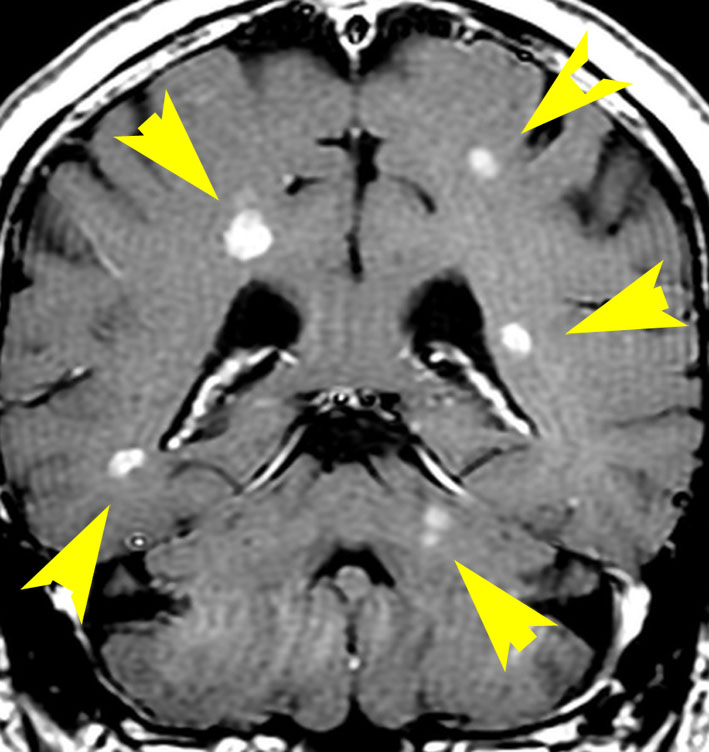

乳癌の多発脳転移の例

全脳照射3ヶ月後のMRIです。左の頭頂葉の転移巣は消失していますし,左の小脳転移は手術摘出できていて再発もありません。このように乳癌は,多発転移であっても比較的に制御しやすいものです。しかし,一度消えた病巣が再発したり,また新たなところに脳転移が生じるという可能性もあります。